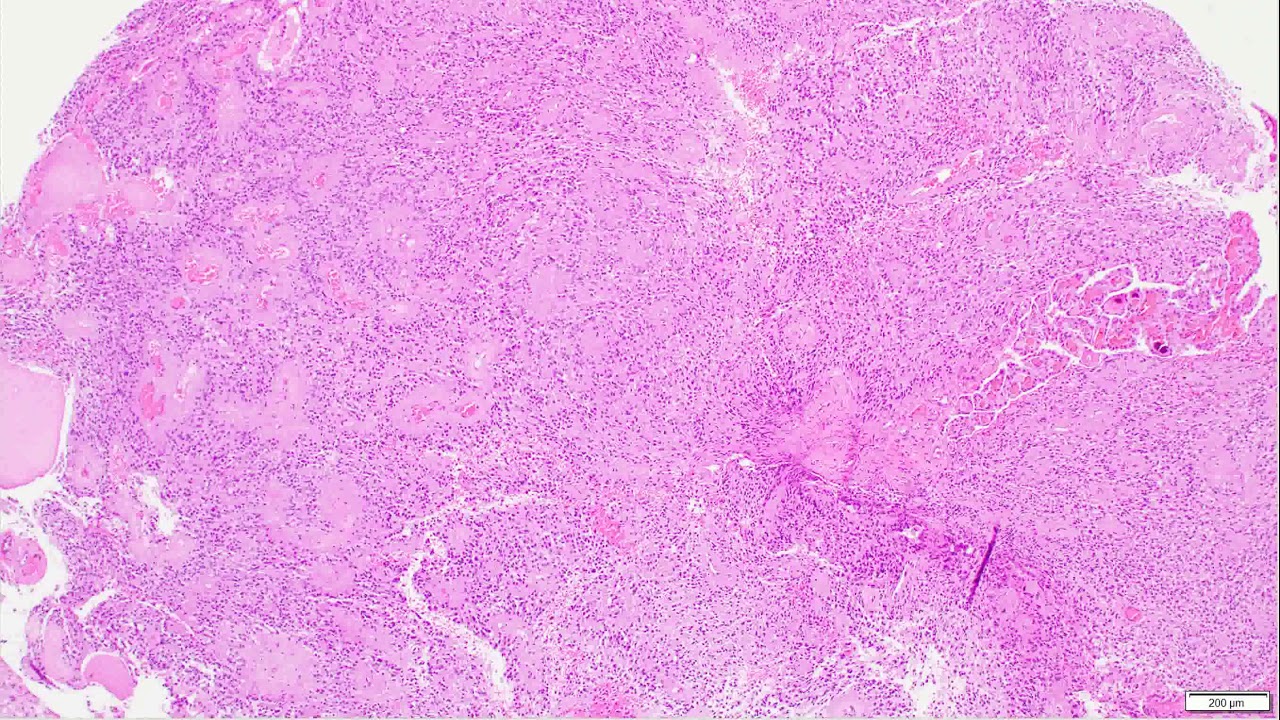

Описание: Ependymomas are glial tumors that commonly harbor perivascular pseudo-rosettes, seen here, characterized by radially arranged tumor cells around a blood vessel core. To learn more about these WHO grade 2 tumors.